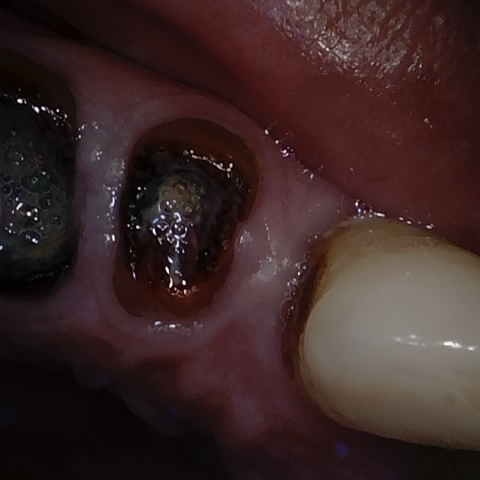

NHD36692

Annotated as "Good"